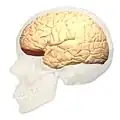

Lateral view.

Lateral view.